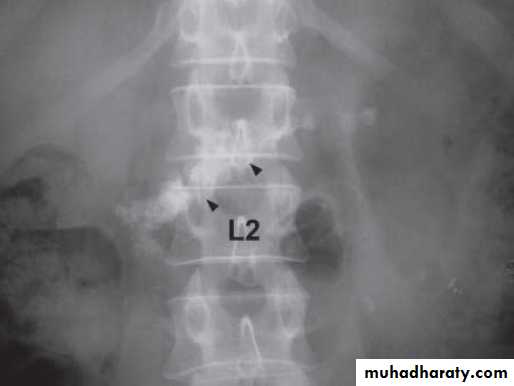

Magnified AXR shows a cluster of coarse calcification (arrowheads) along the perceived location of the pancreas (L1 and L2 levels).